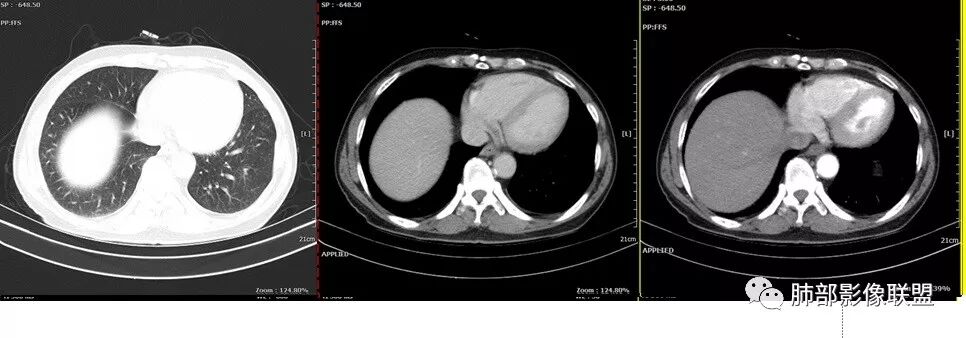

老年男性,反复咳嗽咳痰十余年,加重伴发热5天,胸痛2天。既往有糖尿病病史。白细胞不高,肝功能受损,CRP及igE明显增高。左肺上叶大片磨玻璃影伴局部实变,支气管通畅,右肺下叶背段近端支气管旁不规则实性结节,轻度均匀强化,背段支气管受压变窄,纵隔及双肺门多发淋巴结肿大并钙化。考虑左上肺感染性病变,先抗感染复查,继续查病原体。右下肺背段结节建议经TBLB活检,排外肿瘤。

胸CT:左肺上叶前段实变,其周围及左肺上叶尖后段可见肺气肿背景下渗出性病变,病灶内可见支气管扩张,气道壁呈不规则增厚,双肺散在小结节状影;右肺下叶结节影,内可见空泡,边缘模糊,不规则。增强可见病灶内血管造影征,右肺门增大,纵隔淋巴结多发肿大。

患者中老年男性,发热,咳嗽5天,胸痛2天。慢性咳嗽,咳痰10余年,目前出现活动后胸闷气短,有基础糖尿病、高血压病史,查白细胞正常,CRP增高,IGE增高,CEA轻度增高。胸部CT:左肺上叶片状密度增高影,边界清楚,内血管穿行,呈蜂窝网格状,内有磨玻璃影,部分支气管壁增厚,部分有扩张,部分有近段粗细不均;右肺下叶可见一结节影,有凹陷,有膨隆,似有结节感,右侧肺门淋巴结肿大,纵隔多发淋巴结肿大、部分伴有钙化。综合考虑恶性病变,左上肺粘液腺癌可能,右下肺小细胞癌?两源论考虑:左上肺粘液腺癌或粘膜相关性淋巴瘤?右下肺结核球伴肺门淋巴结肿。

老年男性,有糖尿病4年,长期咳嗽;这次咳嗽5天,左胸痛2天

这个病灶如何考虑?

纵膈淋巴结以钙化为主。

这个壁厚,但是支气管软骨连续。

背段支气管有问题,局部有结节

膈面上还有一个结节

总共4处病灶,如何考虑?

左上叶肿瘤?炎性?

还有少量胸水。

第一个问题:左上叶考虑炎症?癌?

实变区:

实变区边缘收缩,部分区域紧贴纵隔胸膜。

胸膜下有间隙

左肺上叶病灶长轴与支气管走形一致,提示沿支气管分布病变,倾向于炎性,大家可能怀疑这个病例是来源于胸膜下为主的,胸膜下来源首先整体是来源于胸膜下,与胸膜下之间没有间隙,而这例与胸膜下有间隙。而且这个病变是沿支气管朝外蔓延的,而胸膜下来源的是朝内蔓延的,唯一给我们错觉的是靠近纵隔胸膜这个地方有问题。但是靠近纵隔胸膜这个位置实变不是靠近胸膜实变,它边缘收缩的,没有膨隆的迹象。我们看到里面支气管直达远端稍扩张,是以中央间质为主、小叶间隔朝外蔓延,有间质也有实质病变,走向是沿中央间质方向走的,我个人倾向炎性病变。    问题是右下叶病灶怎么解释?右隔上、右肺门各有一个结节。这个病人有急性咳嗽、胸痛的病史,还有糖尿病病史,周围渗出比较明显,应该警惕炎性病变,要警惕克雷伯杆菌、结核、金葡菌霉菌,因为糖尿病人经常好发这些病菌感染。那么右下叶病变怎么考虑?能不能一元论?    左肺病灶是一个急性渗出为主的病变,一个急性感染的迹象;右肺下叶背段结节,没有看到支气管,增强图支气管壁增厚,局部小结节,呈分叶状,支气管堵塞,没有粘液栓样指套样改变,但是里面有强化,我倾向于癌,其次待排结核。我还是倾向于癌的可能性,恶性可能性大一些,可惜我看不到支气管腔内。还考虑有没有淀粉样变性的问题,弥漫钙化灶最常见的一个是结核,另一个是淀粉样变性。叶段支气管壁有弥漫增厚的迹象。所以淀粉样变性跟结核都要考虑。